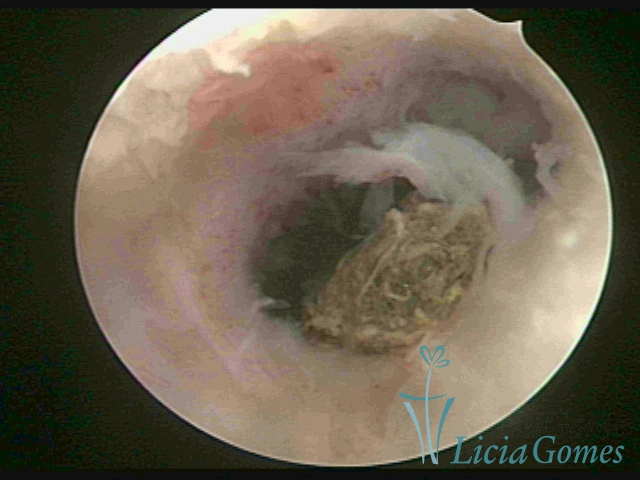

Cavidade uterina com resíduo de DIU, fragmentado, colocado há 46 anos